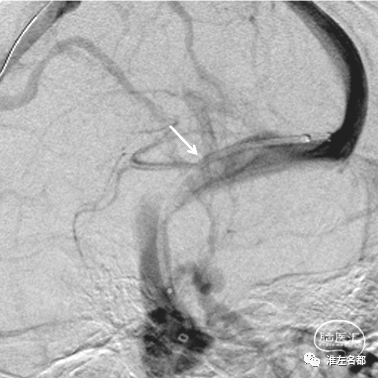

上述的球囊在负压下沿微导丝送至上矢状窦后部,以此为支撑,将中间导管头端推送至右侧横窦远心侧(橙箭),撤出球囊;沿微导丝将Wallstent支架(7.0*40mm,波科)通过中间导管送至右侧横窦狭窄处(白箭),造影证实定位准确。

逐步缓慢回撤中间导管和释放支架,期间需经颈动脉造影静脉相观察支架位置(白箭)是否准确。